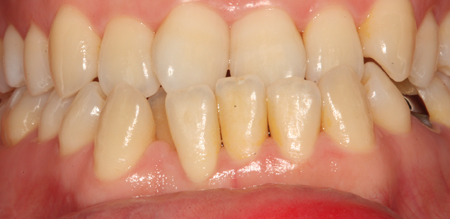

치주치료 전후사진

B

A

치주치료

청담네오플란트는 치주치료를 통하여 치아를 살릴 수 있는 기회를 놓치지 않습니다.

치주염(잇몸병)은 치아에 붙어있는 치석 및 세균 등에 의한 염증반응으로 잇몸뼈가 상실되는 질환을 말합니다.

초기에는 잇몸이 붓거나 잇몸에서 피가 나는 증상이 나타나며 계속 방치하면 치아를 발치해야 할 수도 있습니다.

치주치료는 이러한 치석 및 세균 등을 제거하여 잇몸뼈를 안정된 상태로 유지하는 시술을 말하며, 청담네오플란트에서는 치의학박사 / 전문의가 직접 시술하고 있습니다.